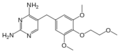

- 220px-Magnesium pyridoxal 5-phosphate glutamate.png سلام المجذوب

05:23، 10 سبتمبر 2012

220 × 158؛ 6 كيلوبايت